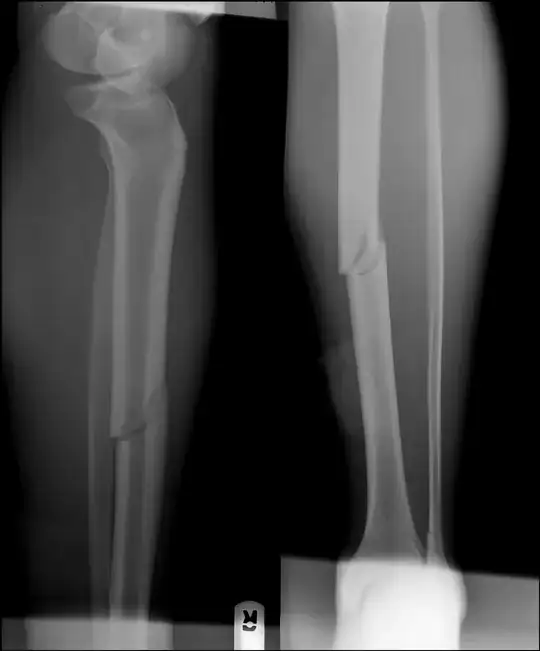

"Breaking" the fibula (or fibular ostotomy) in cases of tibial non-union is not unheard of, but I have absolutely no idea of how often it's done, or if the additional weight-bearing associated with it speeds tibial healing. But please note that you already have an angulated distal fibular fracture (look at the bone - the fibula - behind the tibia just above its concave surface in the leg on the left.) It looks to be at about 20°.

Also note that the tibial stress fractures - the fracture lines perpendicular to the plane of the tibial fracture itself - are more prominent in the second set of x-rays (this may just be picture quality), as well as more prominent displacement of your fracture, which is easier to see if you follow the medullary lines - the "hollow" inner part of the bone where the bone marrow is - you'll see they line up nicely in the first set of x-rays, less so in the second.